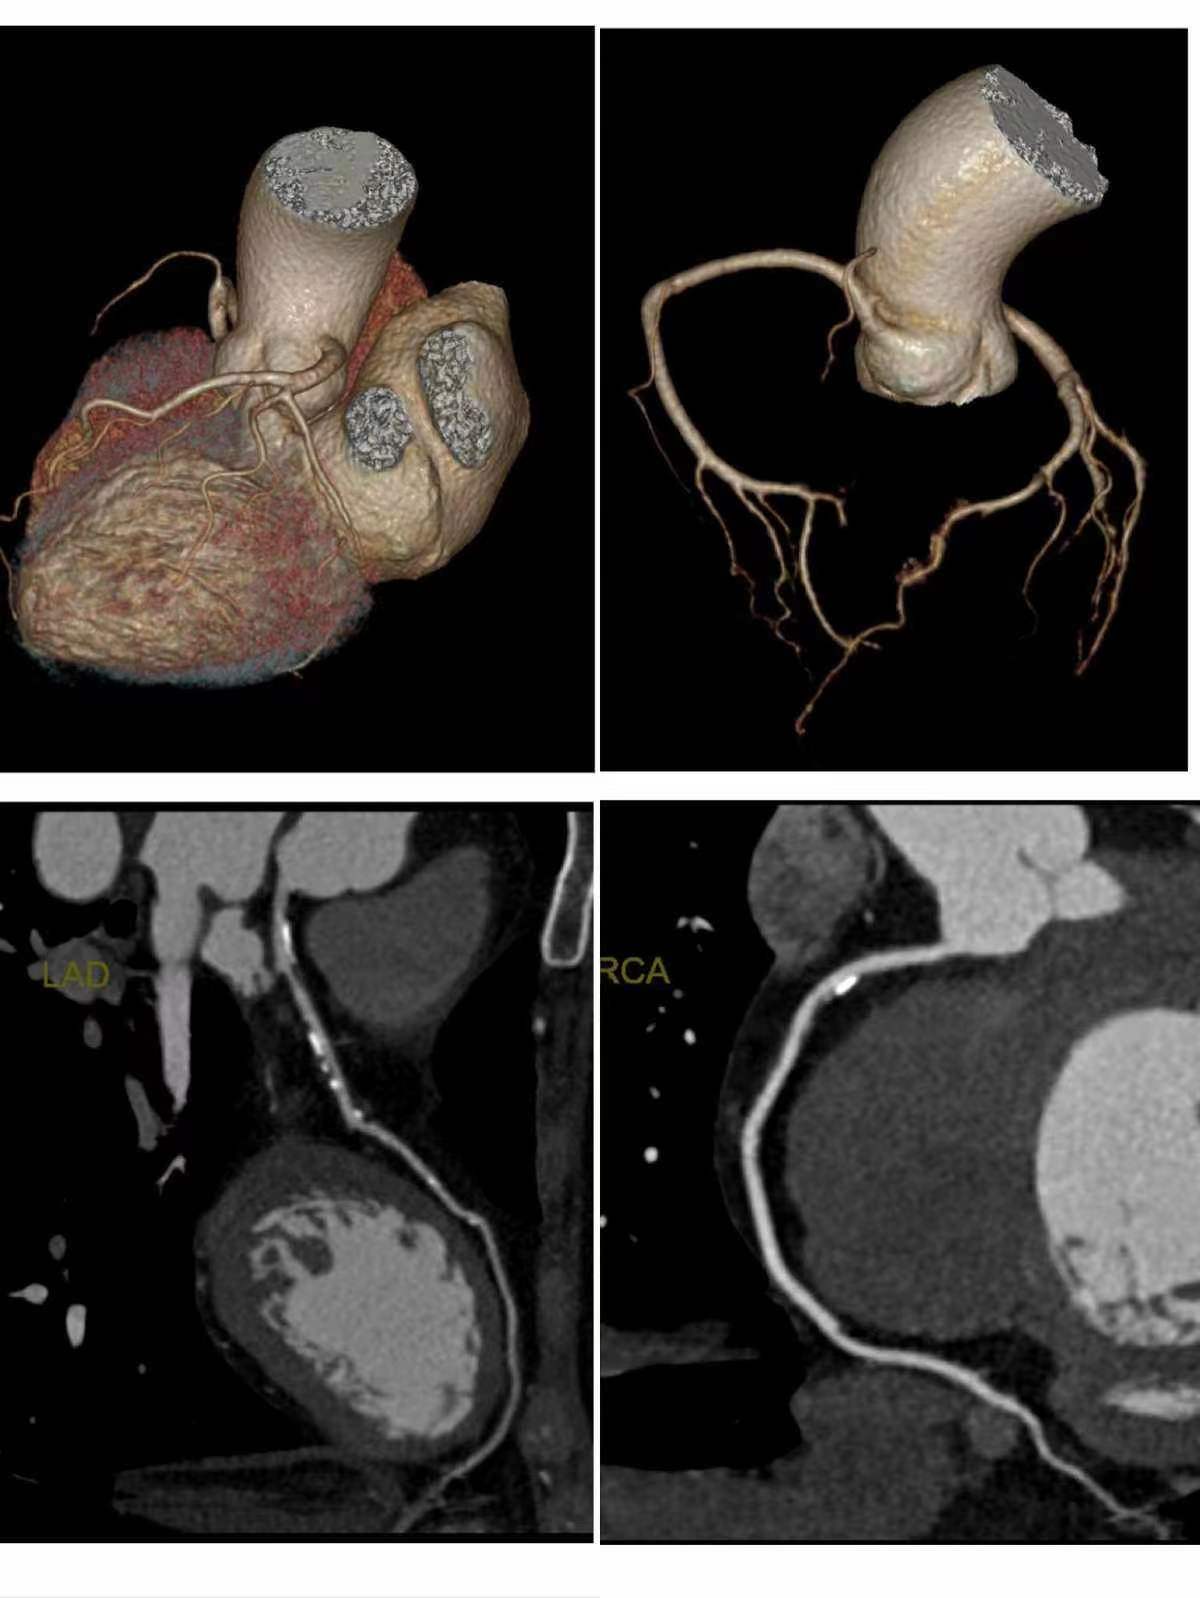

冠脉CTA检查是一种无创检查,通过经静脉注射造影剂后利用螺旋CT扫描再经计算机处理重建得出心脏冠状动脉成像。该检查主要用于冠心病的筛查,能够明确诊断患者有无冠状动脉狭窄,并评价斑块的性质与狭窄的程度。

图像后处理包括原始图像重建、判读图像和检查质量、三维重建和后处理等步骤,以确保检查结果的准确性和可靠性。